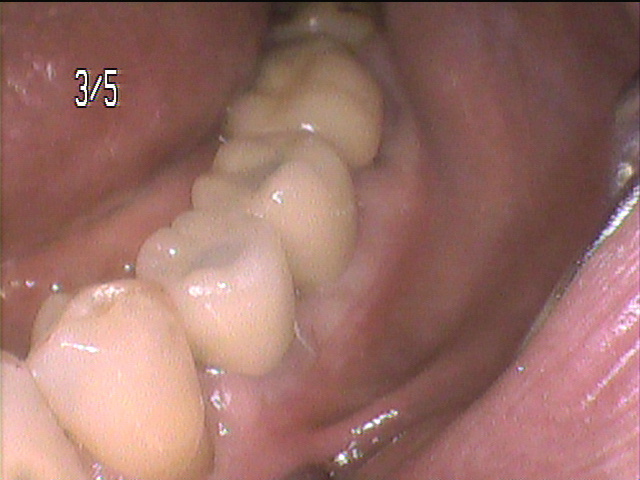

- 術後の口腔内写真です。

本来歯牙があった部分に職立され、審美的にも機能的にも適切に植立されています。